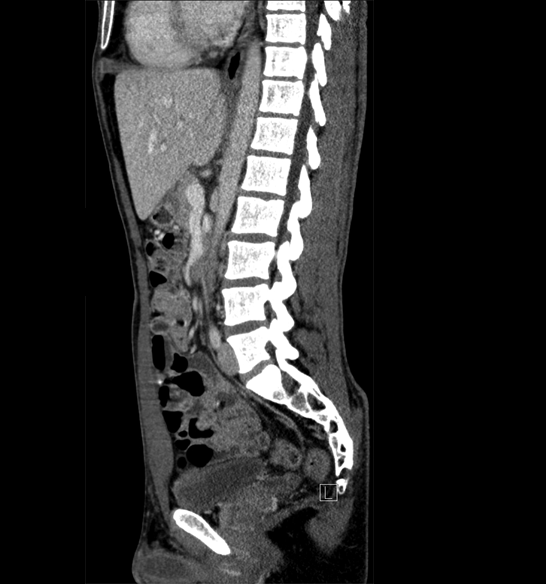

Body

Covers abdominal CT anatomy.